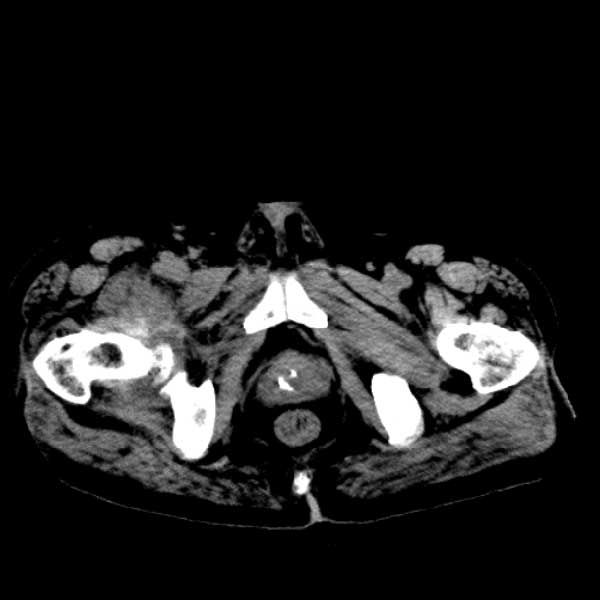

标题: CT13513:男 71 腹部疼痛20余天,近几天高热就诊,骨窗未见异 [打印本页]

标题: CT13513:男 71 腹部疼痛20余天,近几天高热就诊,骨窗未见异

考虑感染性病变可能性大,起源于阑尾?

感染,脓肿形成

考虑为化脓性阑尾炎.脓肿形成.及多肌肉累及.

考虑右侧腰大肌脓肿,向右髂窝、右腹股沟流注。

支持化脓性阑尾炎伴右髂窝脓肿、腰大肌腰方肌脓肿形成。

考虑腹腔及盆腔化脓性炎症,累及右侧髋关节及腹股沟区.

首先考虑化脓性阑尾炎伴腰大肌、腰方肌脓肿,不除外回盲部结核。

回盲部癌待排除。

患者肠镜检查考虑结肠癌,病理证实

患者肠镜检查考虑结肠癌,病理证实。肺部ct可见多发结节,考虑转移